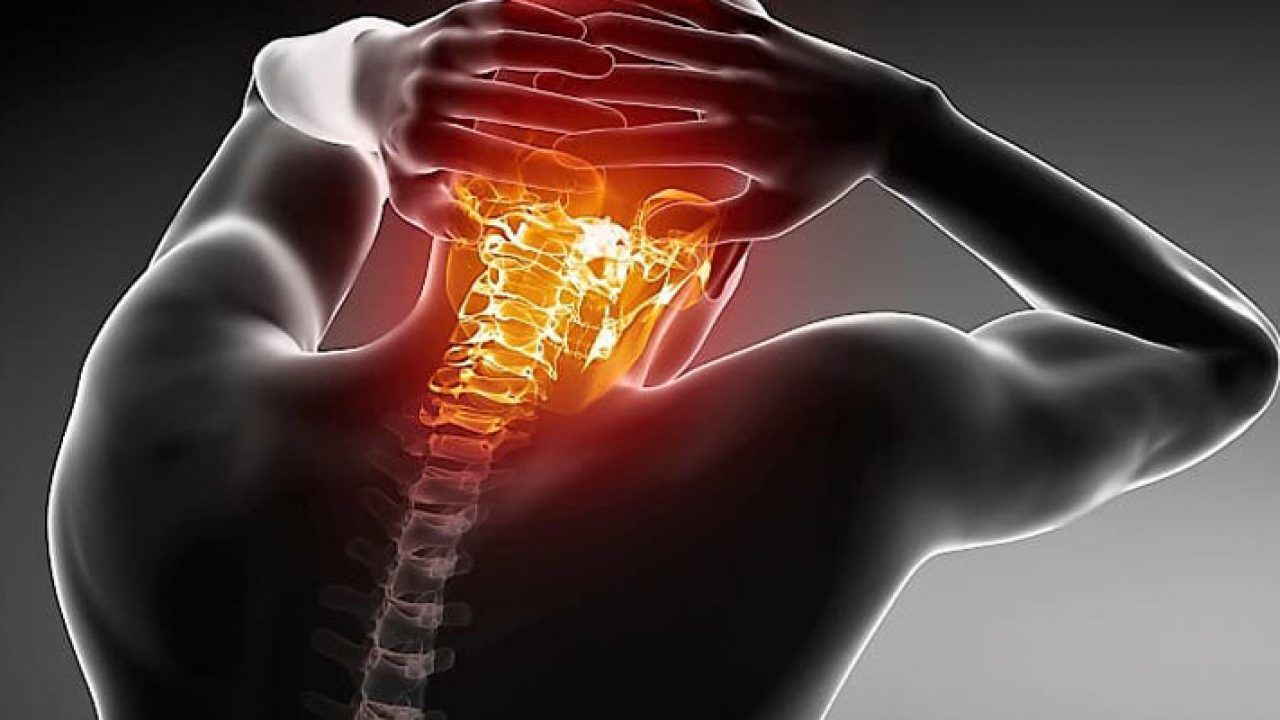

Agendar consulta A cervicalgia, popularmente conhecida como dor no pescoço, é uma queixa extremamente comum. Ela se refere a qualquer desconforto ou dor localizada na